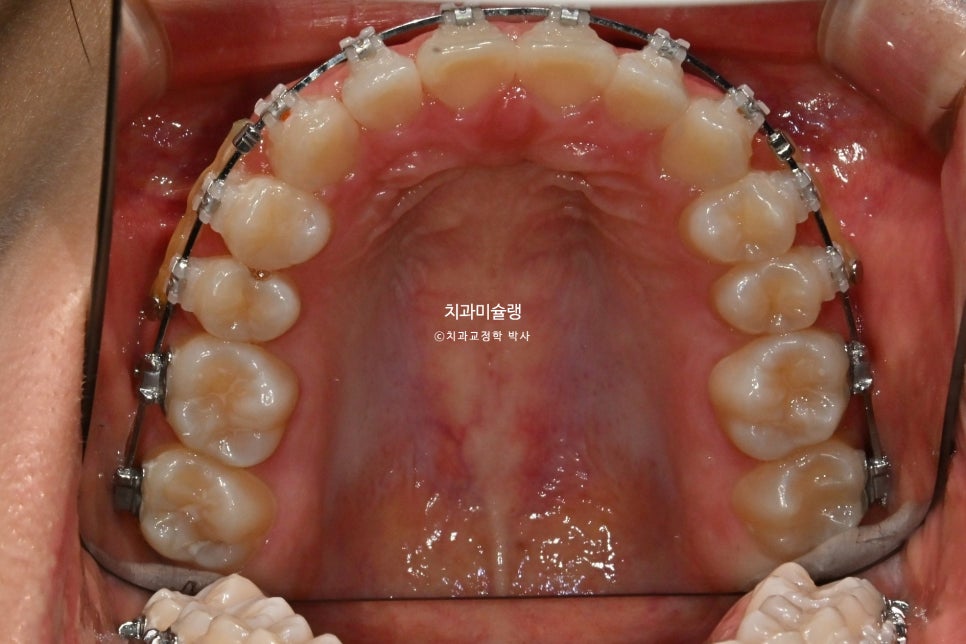

고정용 나사를 4군데 심고 전체치열을 뒤로 당기고 있습니다.

1년 2개월간 치근흡수는 없으며, 치근평행도는 양호합니다. 사랑니 공간으로 어금니들이 잘 이동하였습니다.